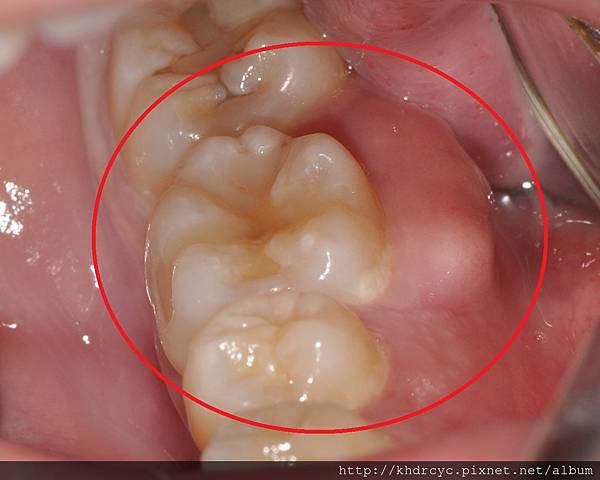

只要局部清潔洗牙

把膿包旁邊的牙結石 塞住的牙垢清掉

搭配膿包沖洗 三天左右就會消掉

但發生牙周膿腫就凸顯出

過去的清潔習慣有蠻大的問題

腫大的地方是清潔的死角

消腫之後常可以明顯看到殘留的牙結石

若不改進清潔習慣 往往還會再發